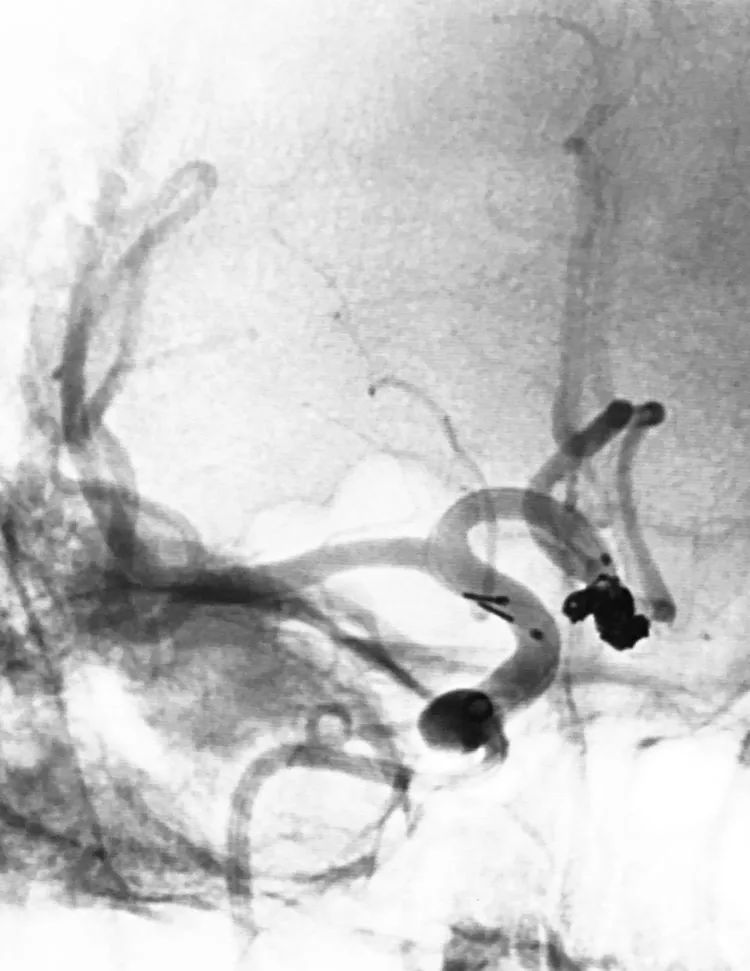

2019年3月13日行DSA+介入治疗。术前左颈内动脉造影三维重建显示左侧后交通动脉瘤,呈牛角形分叶;后交通动脉由瘤颈近心端发出,非胚胎性:

测量,公共瘤颈宽5.40 mm,大分叶4.86 mm×6.35 mm,小分叶3.57 mm×4.28 mm,可视为两个孤立的小型动脉瘤,分而治之:

计划支架结合双微导管技术栓塞。6F Navien中间导管在6F长鞘支撑下抵达左颈内动脉破裂孔段。左颈内动脉工作位(LAO 52°)路图下,经Navien送入三套微导管,Headway-21支架导管进入左大脑中动脉;第一根Echelon-10微导管(甲管,头端塑成C形)在Synchro-14微导丝引导下进入大分叶;第二根Echelon-10微导管(乙管,头端塑成猪尾形)进入小分叶:

LVIS支架(3.5-15)辅助下双微管栓塞动脉瘤,先经甲管向大分叶内依次填入5枚弹簧圈(QC-6-15-3D,4-12-HELIX,3-8-HELIX,3-8-HELIX,2-8-HELIX),少量弹簧圈挤入小分叶;再经乙管向小分叶内依次送入3枚弹簧圈(APB-3-8-3D-ES,2-6-HX-ES,1.5-4-HX-ES);最后继续经乙管送入3枚弹簧圈(APB-1.5-3-HX-ES,1-3-HX-ES,1-3-HX-ES)封闭瘤颈:

术后左颈内动脉工作位造影显示动脉瘤完全栓塞,后交通动脉壶腹保留: